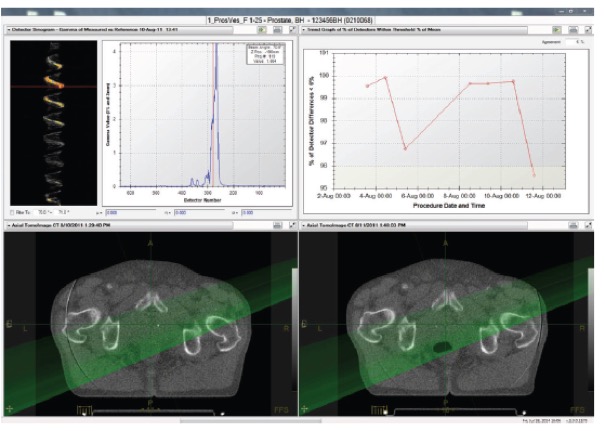

III. Οι κύριες παράμετροι του συστήματος PreciseART είναι:

I. Χρήση εικόνων MVCT για την ποσοτικοποίηση της επίδρασης των ανατομικών και βιολογικών μεταβολών του ασθενούς

- Αυτόματη σύντηξη των καθημερινών εικόνων αξονικής τομογραφίας με τις αντίστοιχες εικόνες σχεδιασμού της θεραπείας του ασθενούς.

- Ενσωμάτωση στους υπολογισμούς των καθημερινών μετακινήσεων για την ακριβή τοποθέτηση του ασθενούς σε θέση θεραπείας

- Αυτόματος υπολογισμός της χορηγούμενης κατανομής δόσης στον ασθενή με βάση της καθημερινές εικόνες αξονικής τομογραφίας

II. Αυτόματη παρακολούθηση της χορηγούμενης ακτινοθεραπευτικής αγωγής

Το σύστημα περιλαμβάνει εργαλεία που επιτρέπουν στον ακτινοθεραπευτή ιατρό να παρακολουθεί την εκτέλεση της ακτινοθεραπείας και να ενημερώνεται αυτόματα για τις περιπτώσεις εκείνες που απαιτείται αναπροσαρμογή του πλάνου θεραπείας.

Το σύστημα περιλαμβάνει εργαλεία που επιτρέπουν στον ακτινοθεραπευτή ιατρό να παρακολουθεί την εκτέλεση της ακτινοθεραπείας και να ενημερώνεται αυτόματα για τις περιπτώσεις εκείνες που απαιτείται αναπροσαρμογή του πλάνου θεραπείας.

- Σύντηξη των παραμέτρων του πλάνου θεραπείας (π.χ., περιγράμματα στόχου και κρίσιμων οργάνων) με τις καθημερινές εικόνες αξονικής τομογραφίας λαμβάνοντας υπόψη τις ανατομικές και βιολογικές μεταβολές του ασθενούς

- Υπολογισμός της καθημερινά χορηγούμενης κατανομής δόσης

- Υπολογισμός της αθροιστικά χορηγούμενης δόσης

- Ενημέρωση της ηλεκτρονικής καρτέλας του ασθενούς για την δοσιμετρική ακρίβεια της χορηγούμενης ακτινοθεραπείας

- Ενημέρωση του ακτινοθεραπευτή ιατρού στην περίπτωση που ο όγκος στόχος ή τα κρίσιμα όργανα λαμβάνουν δόση εκτός των κριτηρίων ανοχής που έχει θεσπίσει.

- Αξιολόγηση της ευθυγράμμισης του ασθενούς σε θέση θεραπείας.

- Αξιολόγηση των ανατομικών και βιολογικών μεταβολών του ασθενούς κατά τη διάρκεια της ακτινοθεραπευτικής αγωγής

- Αξιολόγηση της καθημερινά χορηγούμενης κατανομής δόσης, της αθροιστικής δόσης μέχρι την συγκεκριμένη συνεδρία καθώς και των δοσιμετρικών διαφορών

I. Delivery Analysis

Το σύστημα Delivery Analysis επεξεργάζεται με τρόπο αυτόματο τα δεδομένα από την εκτέλεση της θεραπείας κάθε ασθενούς και ελέγχει αν κάθε συνεδρία αποδίδεται όπως έχει σχεδιαστεί.

- Για κάθε ασθενή, το Delivery Analysis ελέγχει τη σωστή λειτουργία του κατεθυντήρα πολλαπλών φύλλων χρησιμοποιώντας το σήμα του ενσωματωμένου ανιχνευτή του συστήματος TomoTherapy. Σε περίπτωση εμφάνισης διαφορών το σύστημα αυτόματα υπολογίζει την επίδραση τους στην κατανομή της χορηγούμενη δόσης και ειδοποιεί τον ακτινοφυσικό και τον ιατρό.

- Σε κάθε συνεδρία το σύστημα μετράει και επεξεργάζεται την ροή φωτονίων στην έξοδο του ασθενούς (exit fluence) για να εξασφαλίσει την σωστή εκτέλεση της θεραπείας από την πρώτη έως την τελευταία συνεδρία.

Εύχρηστο περιβάλλον εργασίας

- Το σύστημα Delivery Analysis αναλύει τα δεδομένα από την εκτέλεση της θεραπείας και τα παρουσιάζει με τρόπο άμεσο και ευανάγνωστο στους ακτινοφυσικούς και του ιατρούς του τμήματος. Το σύστημα ενσωματώνει εργαλεία για την λεπτομερή εξέταση όλων των επιμέρους στοιχείων της θεραπείας συμπεριλαμβανομένων της ακρίβειας τοποθέτησης του ασθενούς, την επίδοσης του συστήματος TomoTherapy κτλ.

Ποιοτικός έλεγχος της ακρίβειας χορήγησης της θεραπείας

- Κατά την διάρκεια εκτέλεσης κάθε συνεδρίας και για κάθε ασθενή το σύστημα Delivery Analysis μετράει αυτόματα με τον ενσωματωμένο ανιχνευτή την ροή των φωτονίων στην έξοδο του ασθενούς

- Το σύστημα Delivery Analysis αναλύει και επεξεργάζεται αυτόματα την ροή των φωτονίων στην εξόδου του ασθενούς ώστε να εξασφαλίσει την σωστή εκτέλεση κάθε συνεδρίας της θεραπευτικής αγωγής του κάθε ασθενούς.